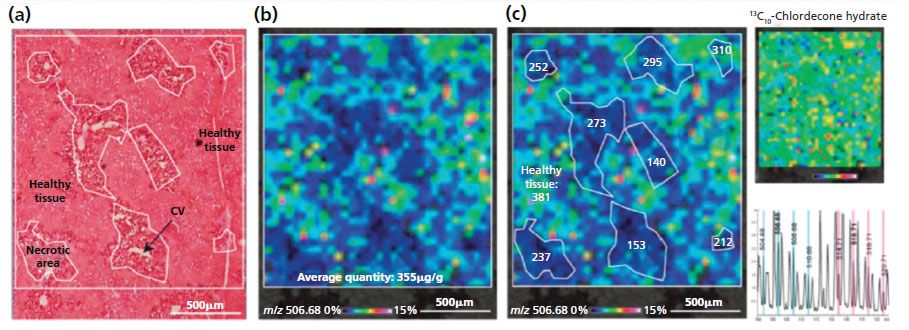

Pineau's team was able to develop a robust method for in situ quantification directly on the tissue sections, published in 2014 (12). Figure 3 shows the in situ absolute quantification method (ISAQ) of chlordecone that was demonstrated in the pathological liver of a chlordecone- and CCl4-treated mouse.

Figure 3: In situ absolute quantification of chlordecone in the pathological liver of a chlordecone and CCl4 treated mouse. (a) Microscopic image of a serial section stained with H&E. (b) MALDI image corresponding to chlordecone hydrate: an average absolute quantity of chlordecone of 355 µg/g was measured in the analyzed area. (c) Local absolute quantities measured in each necrotic areas are lower than those measured in the healthy tissue (381 µg/g). The uniform distribution of the internal standard (m/z 516.71) on the tissue section confirms that the differential distribution of chlordecone is not a result of ion suppression effects.

The group successfully developed a method for the quantification of small molecules by MALDI imaging, based on the combination of labeled normalization with the calculation of a correlation curve between MALDI imaging and GC as a conventional quantification technique. This method was successfully applied to the quantification of chlordecone in the mouse liver, and is the first example of the application of MALDI imaging to the quantification of a pesticide in tissues.